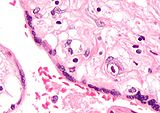

Micrograph of a placental infection (CMV placentitis).